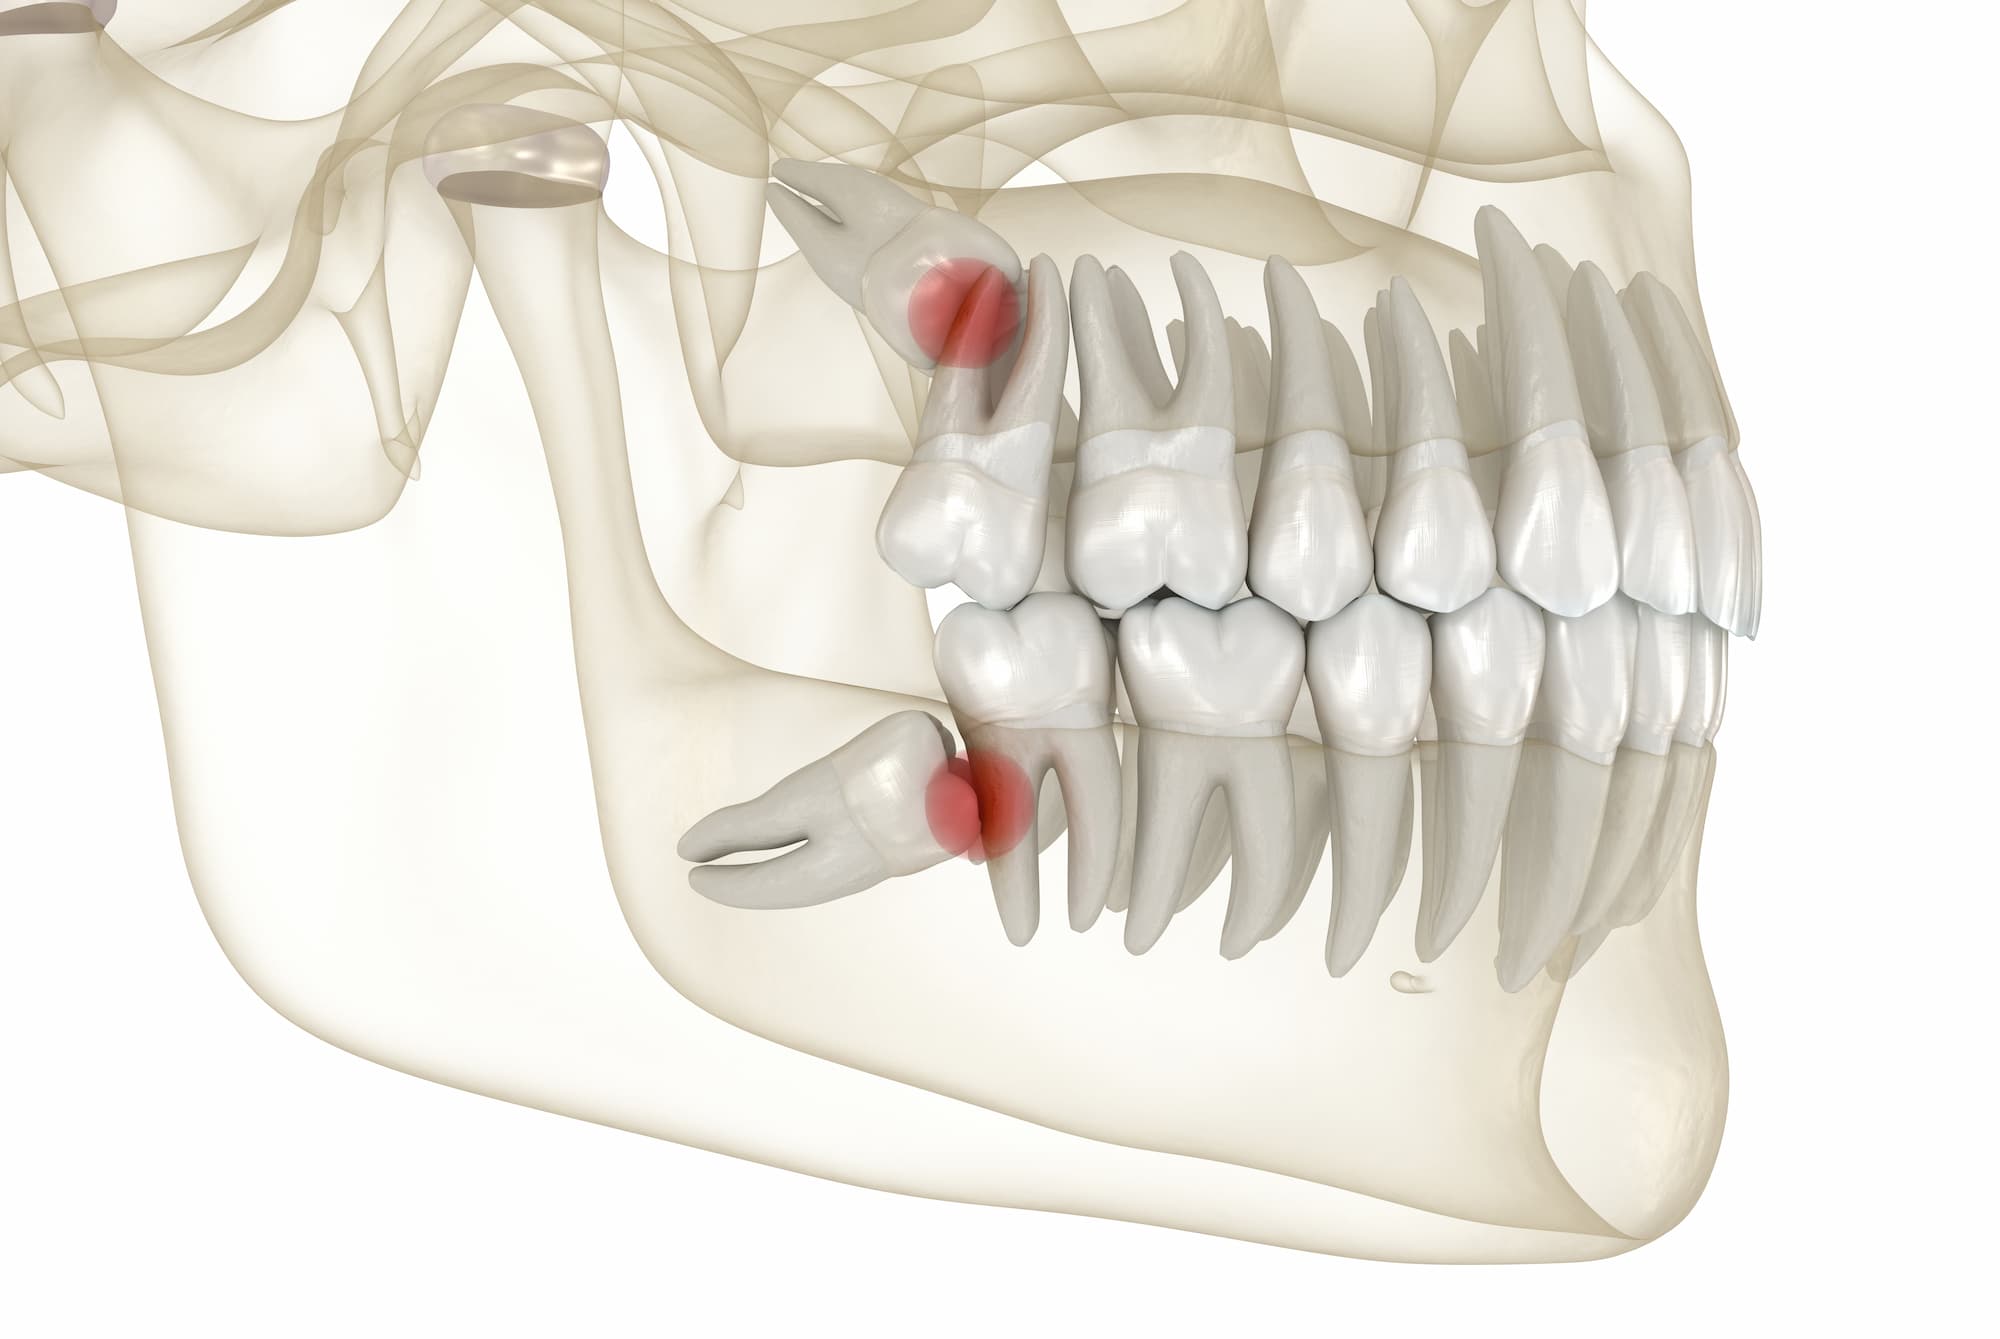

>>220890796I had them removed at age 18, long before they were about to come out, because there was no chance they would fit. And they would have undone all the progress my braces made

>>220890796It's not about the space you have, it's about the position they spawn in

>>220892179If your face is narrow but you have good forward growth you can still have healthy straight teeth. If you have narrow jaw and also very little forward growth it's completely over